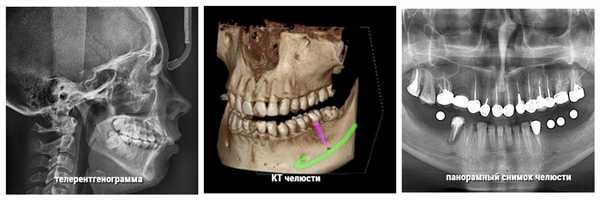

Неправильный прикус у взрослого и ребенка диагностируется с помощью следующих методов исследования:

- панорамный снимок челюсти;

- КТ челюсти;

- телерентгенограмма (ТРГ-снимок).

Перечисленные материалы дают опытному врачу достаточно информации, чтобы определить проблемы с прикусом и составить актуальный план лечения.

Разные виды исследований прикуса